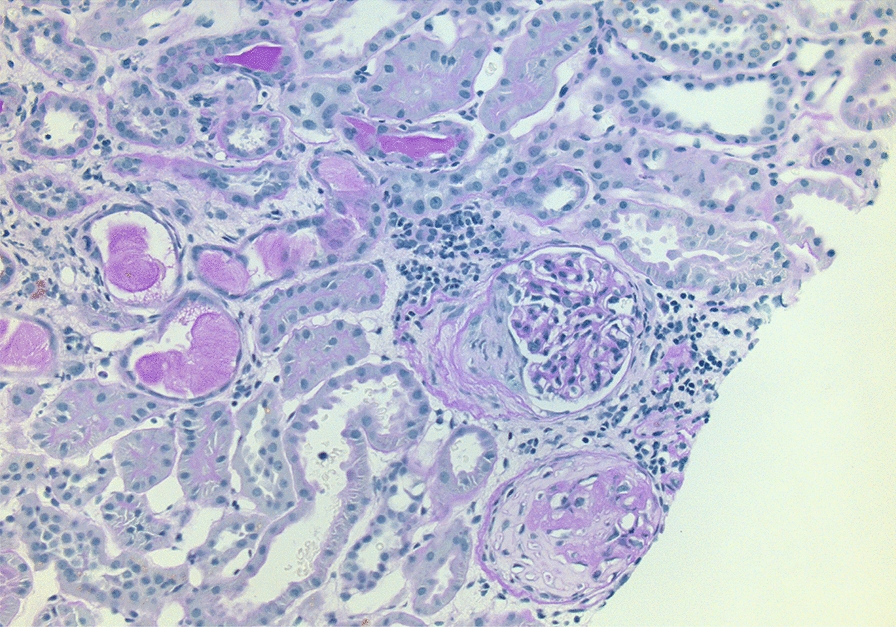

A year later, the PR3-ANCA and ESR increased again to PR3-ANCA of 112 IU/mL and ESR of 41 mm/h. Serum creatinine was 59 µmol/L. The urine dipstick test detected 2 + proteinuria. Examination of the urine sediment displayed hyaline casts and the presence of 3–5 red blood cells and 5–10 leukocytes per field of view. A kidney ultrasound was performed and showed ordinary kidney size, ordinary parenchymal thickness, and increased echogenicity. On the right kidney, a few parapelvic cysts were detected. There were no signs of hydronephrosis. The patient was admitted for kidney biopsy that identified 27 glomeruli, of which one had the morphology of a crescent and one was completely sclerosed; tubular atrophy was between 10 and 15% (Fig. 2). The biopsy further supported the diagnosis of GPA, now with renal involvement. The current symptoms of ear congestion on the right side and occasional nosebleed were mild compared with the initial onset. A high-resolution computed tomography of the lungs revealed no engagement of the lungs. A new computer tomography of the sinus revealed progression of bone destruction in the maxillary sinuses. Altogether, this was interpreted as a relapse of GPA with multi-organ involvement. An Iohexol clearance was not performed; however, the estimated glomerular filtration rate was 89 ml/min/1.73 m2 with serum creatinine of 59 µmol/L as calculated with the Lund–Malmo formula adjusted for age, sex, height, and weight. The dose of Prednisolone was increased to 60 mg followed by de-escalation to 5 mg as a maintenance dose. Additionally, the treatment was intensified with 1000 mg of Rituximab with a second dose after 2 weeks.

Fig. 2.

Histopathological findings of kidney biopsy